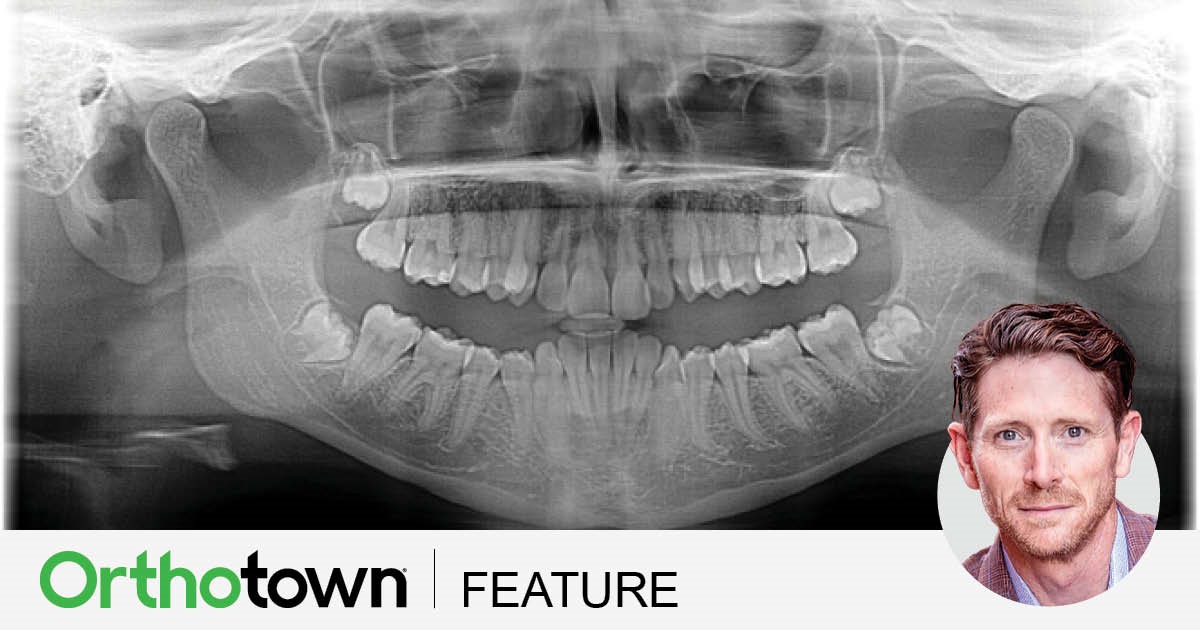

Dr. Robert “Tito” Norris shares techniques for predictable excellence when using a cuspid to replace a missing maxillary lateral incisor. His step-by-step guide is accompanied by a case study, and key considerations to optimize the aesthetics and function of this treatment option.